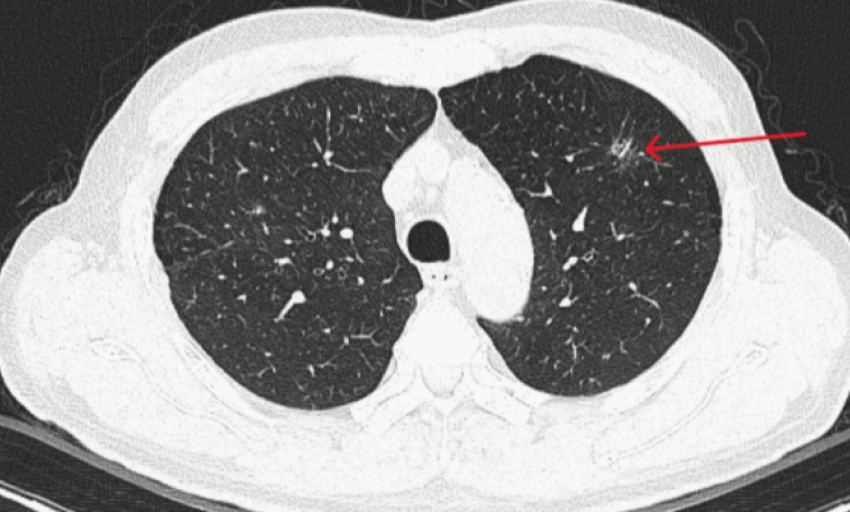

Theo các bác sĩ, thuốc giảm cân của Ngân 98 chứa các chất cấm nguy hiểm như sibutramine, phenolphthalein gây nguy hiểm cho sức khỏe. Những hoạt chất này bị cấm sử dụng trong thực phẩm do có thể gây rối loạn tim mạch, tăng huyết áp, rối loạn tiêu hóa và tiềm ẩn nguy cơ ung thư, ảnh hưởng nghiêm trọng đến sức khỏe người tiêu dùng.

Điểm chung của các ca bệnh này là đều chứa sibutramine - một hoạt chất đã bị cấm sử dụng trên toàn thế giới vì gây hậu quả nghiêm trọng cho tim mạch và thần kinh trung ương.

Theo Bác sĩ Dương Minh Tuấn, Khoa Nội tiết-Đái tháo đường, Bệnh viện Bạch Mai, sibutramine từng được sử dụng trong thuốc điều trị béo phì vì có tác dụng ức chế trung tâm thèm ăn, giúp người dùng giảm cân nhanh. Tuy nhiên, sau một loạt nghiên cứu cho thấy thuốc làm tăng nguy cơ nhồi máu cơ tim, đột quỵ, loạn nhịp tim, tăng huyết áp, rối loạn tâm thần và trầm cảm, Cục Quản lý Dược Mỹ (FDA) và Cơ quan Y tế châu Âu (EMA) đã rút toàn bộ thuốc chứa sibutramine khỏi thị trường từ năm 2010.

Theo bác sĩ Tuấn, có thể nhận biết dấu hiệu ngộ độc sibutramine gồm: Hồi hộp, tim đập nhanh, tăng huyết áp; Mất ngủ, lo âu, kích động, ảo giác; Buồn nôn, đau đầu, vã mồ hôi, run tay.

Trong trường hợp nặng sẽ có dấu hiệu tăng thân nhiệt, loạn nhịp tim, co giật, hôn mê, đột quỵ, thậm chí tử vong.

Nhiều bệnh nhân vào Trung tâm Chống độc (Bệnh viện Bạch Mai) trong tình trạng tăng huyết áp kịch phát, rối loạn nhịp tim, men tim tăng cao, suy gan-thận cấp sau khi dùng thuốc giảm cân chỉ vài ngày.